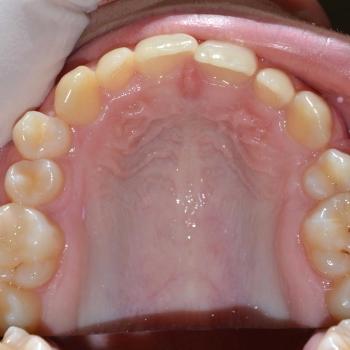

Benjamin és édesanyja az alsó és felső fogíven tapasztalható torlódás miatt kerestek fel, ám az első vizsgálat alkalmával fény derült a jobb felső 5-ös fog csírahiányára, mélyharapásra és féloldali Angle II-es harapási eltérésre is.

A kezelést hagyományos fém fogszabályozóval kezdtük el, melyet bite turbo harapásemelővel egészítettünk ki. A kezelés későbbi fázisában a szimmetria megteremtése érdekében eltávolításra kerül a bal felső maradó 4-es fog is és ezzel párhuzamosan különböző intermaxilláris gumihúzásokat vezettünk be.

Benjamin sportolókhoz méltő fegyelmének köszönhetően a kezelés végére egy esztétikailag és funkcionálisan is kimagasló eredményt érhettünk el.

A kezelés teljes időtartama: 2 év 3 hónap